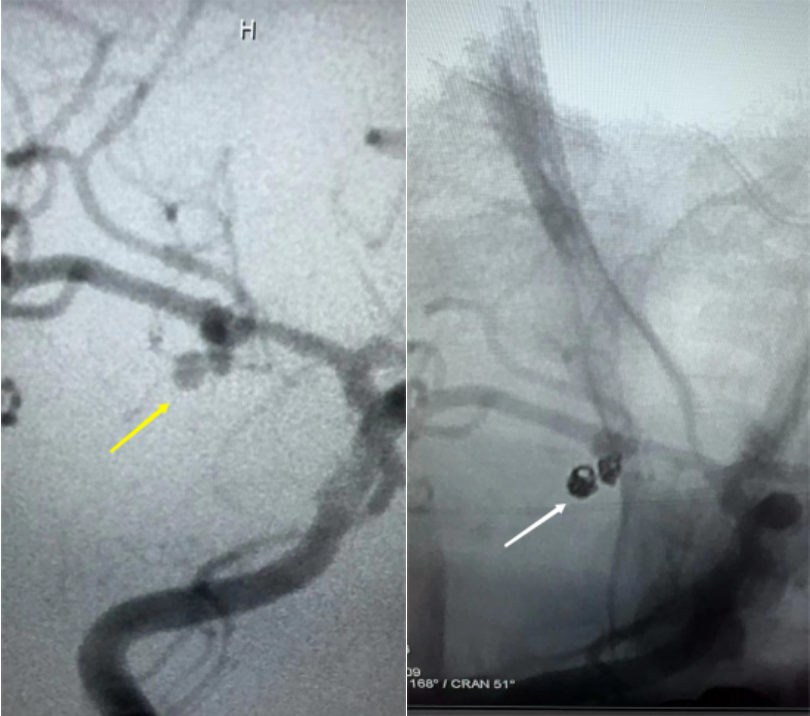

治療方法有血管內(nèi)介入治療、開顱動脈瘤夾閉兩種。目前血管內(nèi)治療即神經(jīng)介入手術(shù),具有恢復(fù)快、創(chuàng)傷小的優(yōu)點(diǎn),已經(jīng)成為大多數(shù)患者的首選治療方式。

本周破裂動脈瘤合并子瘤介入栓塞治療(左為手術(shù)前右為手術(shù)后)